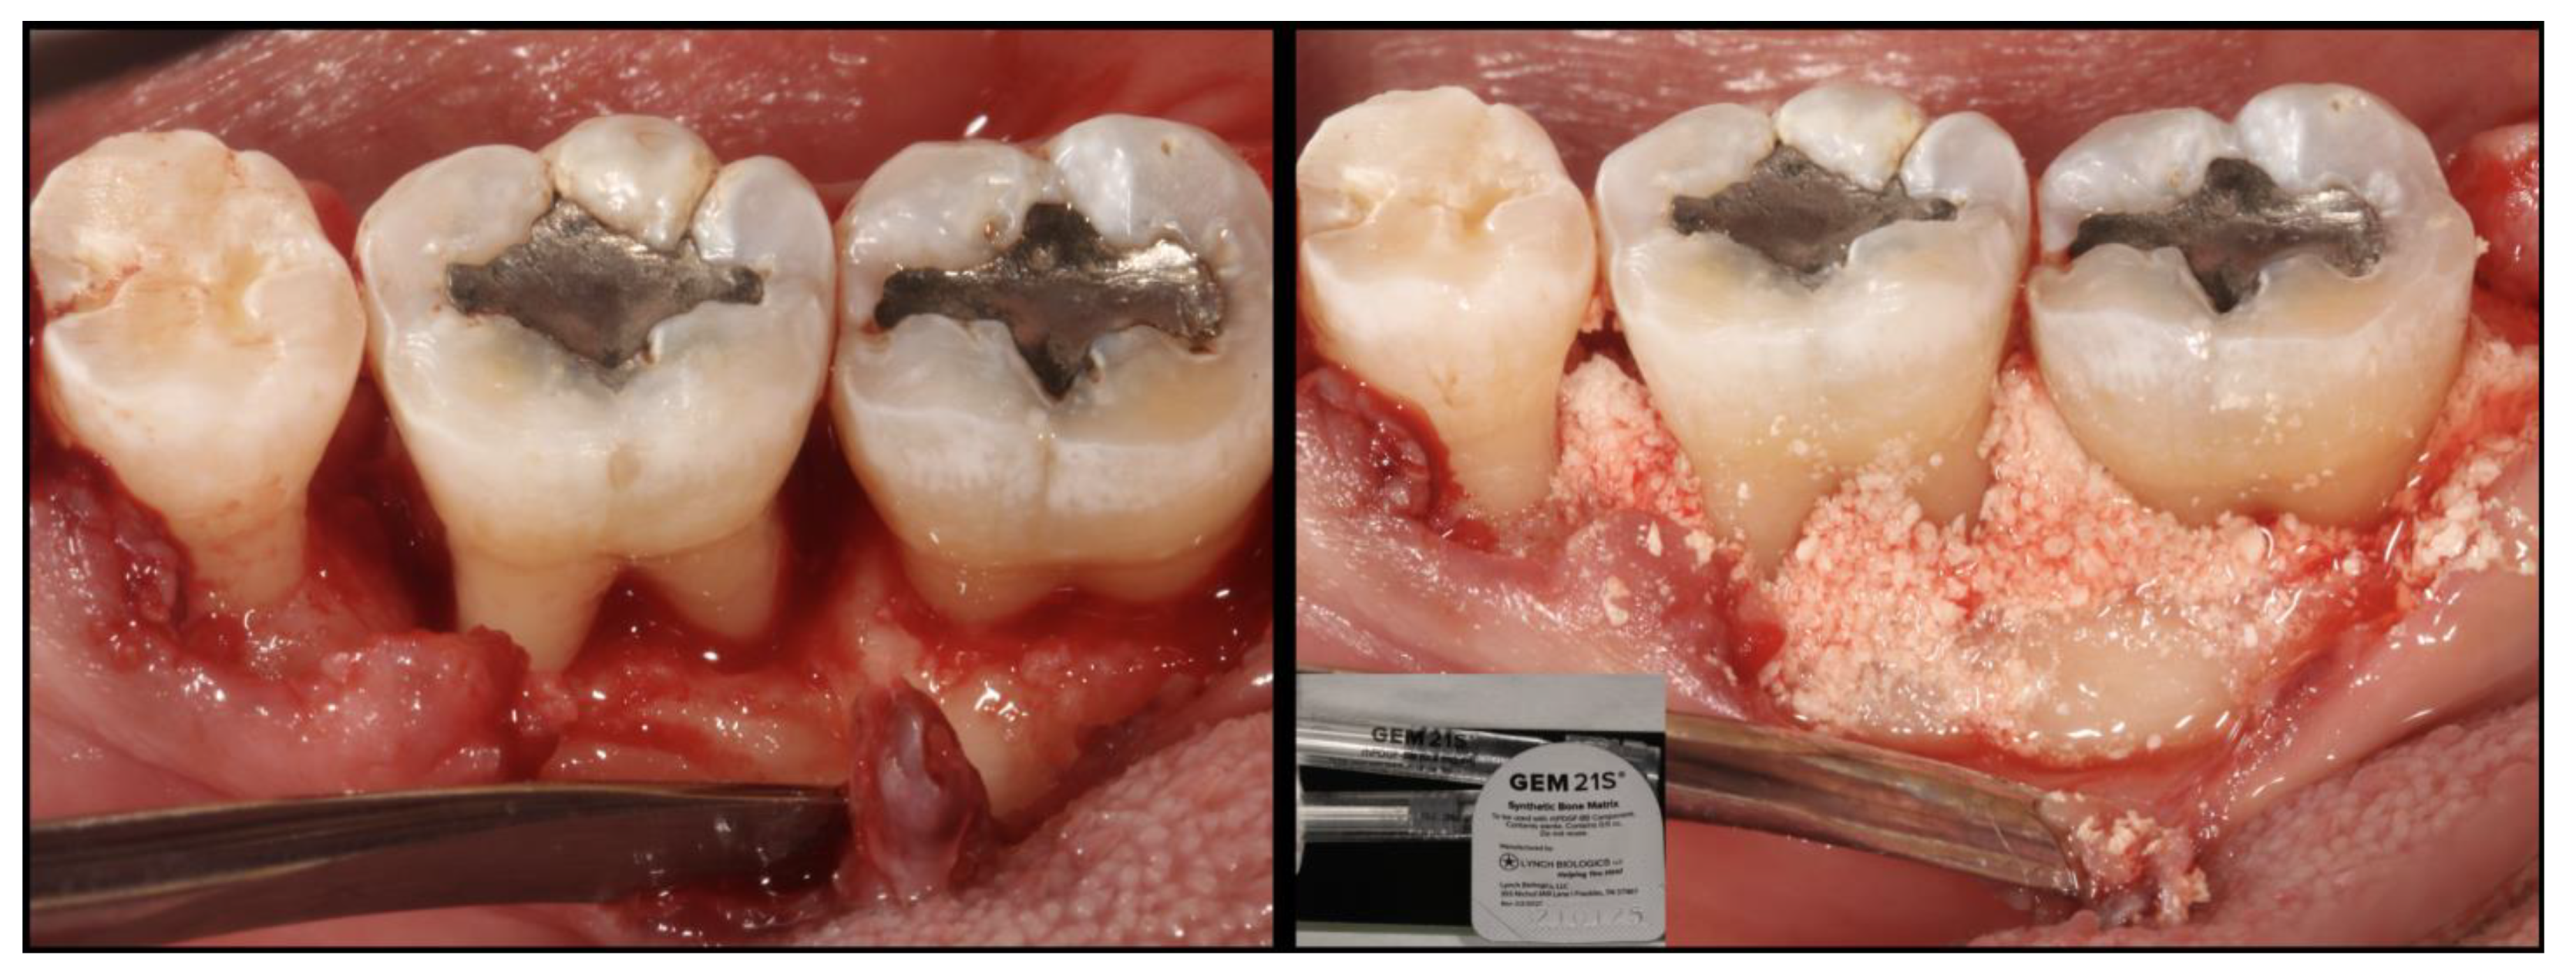

5. Guided Tissue Regeneration with Biologics